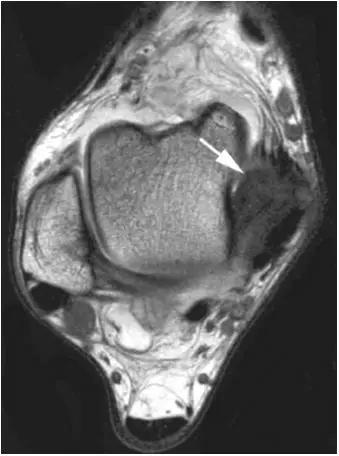

轴位示意图示后内侧撞击综合征:M:内踝;L:外踝;TP:胫后肌腱;FDL:趾长屈肌腱;Talus:距骨。短箭:距骨胫骨间肌腱深层纤维;箭头:距骨胫骨间肌腱后部纤维。

X线平片示胫骨后部骨赘形成,MR质子像黑箭示胫骨内后侧骨赘形成,白箭示内后侧软组织增厚, 白箭头:胫后肌腱;黑箭头:趾长屈肌腱